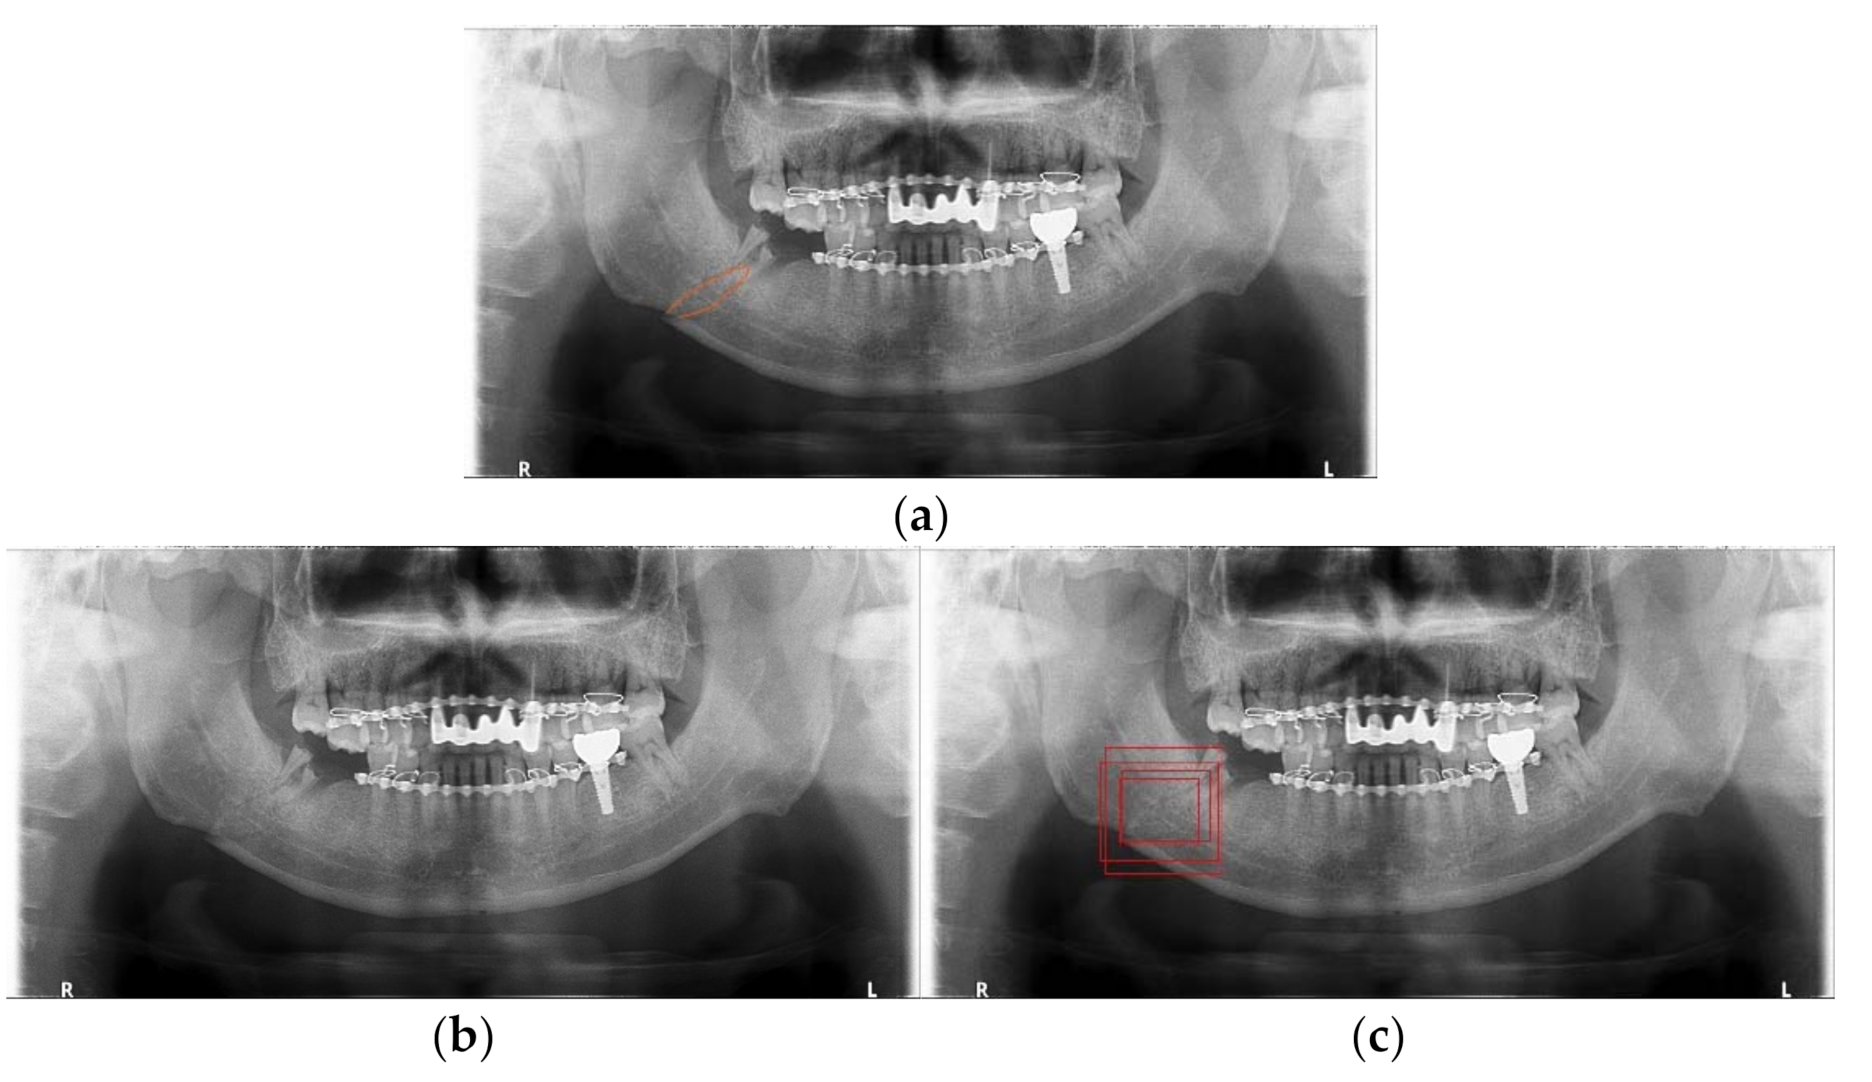

3.2. Detection Results